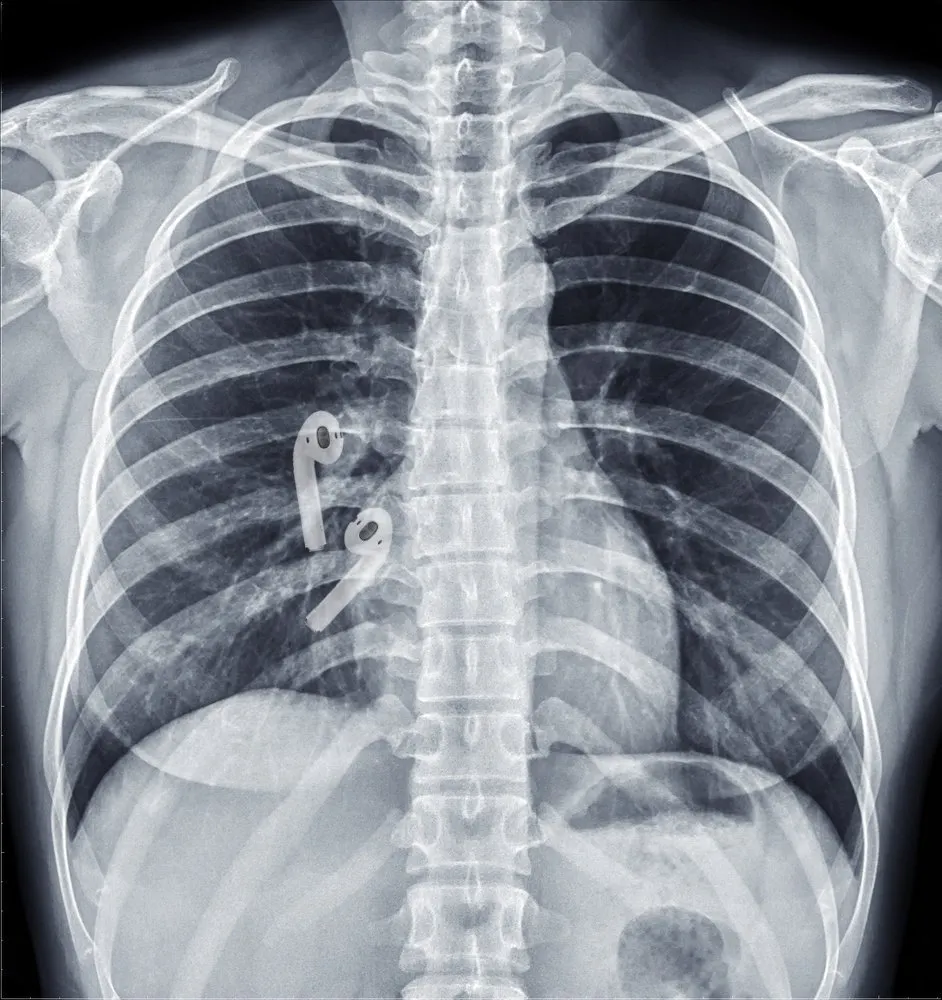

Программа показала, что аксессуар находится где-то рядом: спустя несколько минут Хсу понял, что один «эйрпод» каким-то образом попал к нему в желудок. Врачи, к которым он обратился, подтвердили, что прямо сейчас пищеварительная система пытается переварить несъедобный продукт.

Бену дали слабительное и порекомендовали прийти через сутки, если «эйрподс» не вернется. Все сложилось удачно: наушник вышел естественным путем уже к вечеру. Вот так он выглядел: